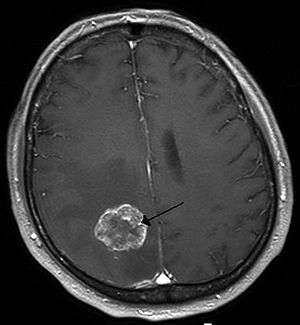

A brainstem glioma in four-year-old. MRI, sagittal, without contrast

Led by Prof. Nori Kasahara, researchers from USC, who are now at UCLA, reported in 2001 the first successful example of applying the use of retroviral replicating vectors towards transducing cell lines derived from solid tumors.[55] Building on this initial work, the researchers applied the technology to in vivo models of cancer and in 2005 reported a long-term survival benefit in an experimental brain tumor animal model.[56] Subsequently, in preparation for human clinical trials, this technology was further developed by Tocagen (a pharmaceutical company primarily focused on brain cancer treatments) as a combination treatment (Toca 511 & Toca FC). This has been under investigation since 2010 in a Phase I/II clinical trial for the potential treatment of recurrent high-grade glioma including glioblastoma multiforme (GBM) and anaplastic astrocytoma. No results have yet been published.[57]